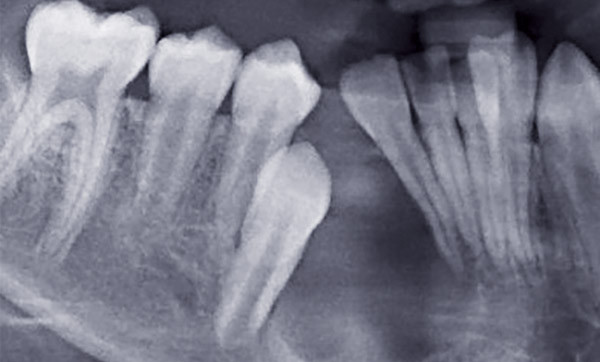

Une dent en rétention est une « dent immature non présente sur l’arcade, à l’âge où elle aurait dû faire son éruption ». Sans traitement, elle peut, en devenant mature, devenir enclavée ou incluse (fig. 1).

Une dent incluse proprement dite est « une dent encore incluse dans l’os maxillaire ou mandibulaire dont l’édification radiculaire apicale s’est terminée avant que le processus d’éruption ne lui ait permis d’évoluer jusque dans le milieu buccal, sans la moindre effraction de la muqueuse orale et sans contamination du sac péricoronaire par la flore bactérienne buccale » (fig. 2). Une dent en désinclusion est définie comme une « dent restée incluse, une grande partie de la vie, jusqu’à ce que certaines transformations morphologiques de la cavité orale favorisent son exposition au milieu buccal » (fig. 2).

Une dent enclavée (terme utilisé principalement en France) est « une dent dont l’édification radiculaire apicale s’est terminée après que le processus d’éruption…